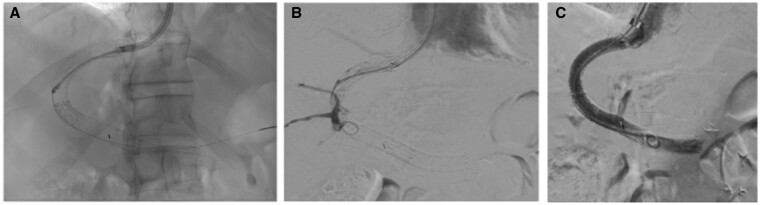

Transjugular intrahepatic portosystemic shunting (TIPS) is an established strategy for the management of complications of portal hypertension. Endoprosthetic infection ("endotipsitis") is a rare but serious and difficult-to-treat complication of TIPS placement. Here we report the occurrence of an infected thrombus complicating TIPS placement in a patient with extra-hepatic portal vein obstruction, recurrent variceal bleeding and portal biliopathy accompanied by recurrent cholangitis. Infected thrombotic material within TIPS could be removed only by employing rotational thrombectomy. This procedure revealed the presence of a biliary fistula which carried pathogens in the systemic circulation. The multiple episodes of sepsis did no longer recur following exclusion of the biliary fistula. This case highlights the possibility to use rotational thrombectomy for the management of complex cases of TIPS dysfunction.